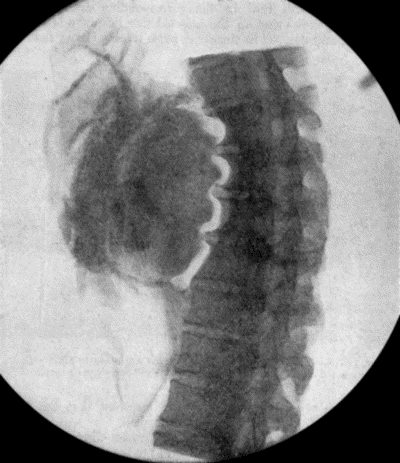

73.Radiogram of Innominate Aneurysm after Treatment by Moore-Corradi method 309

74.Thoracic Aneurysm threatening to rupture 313